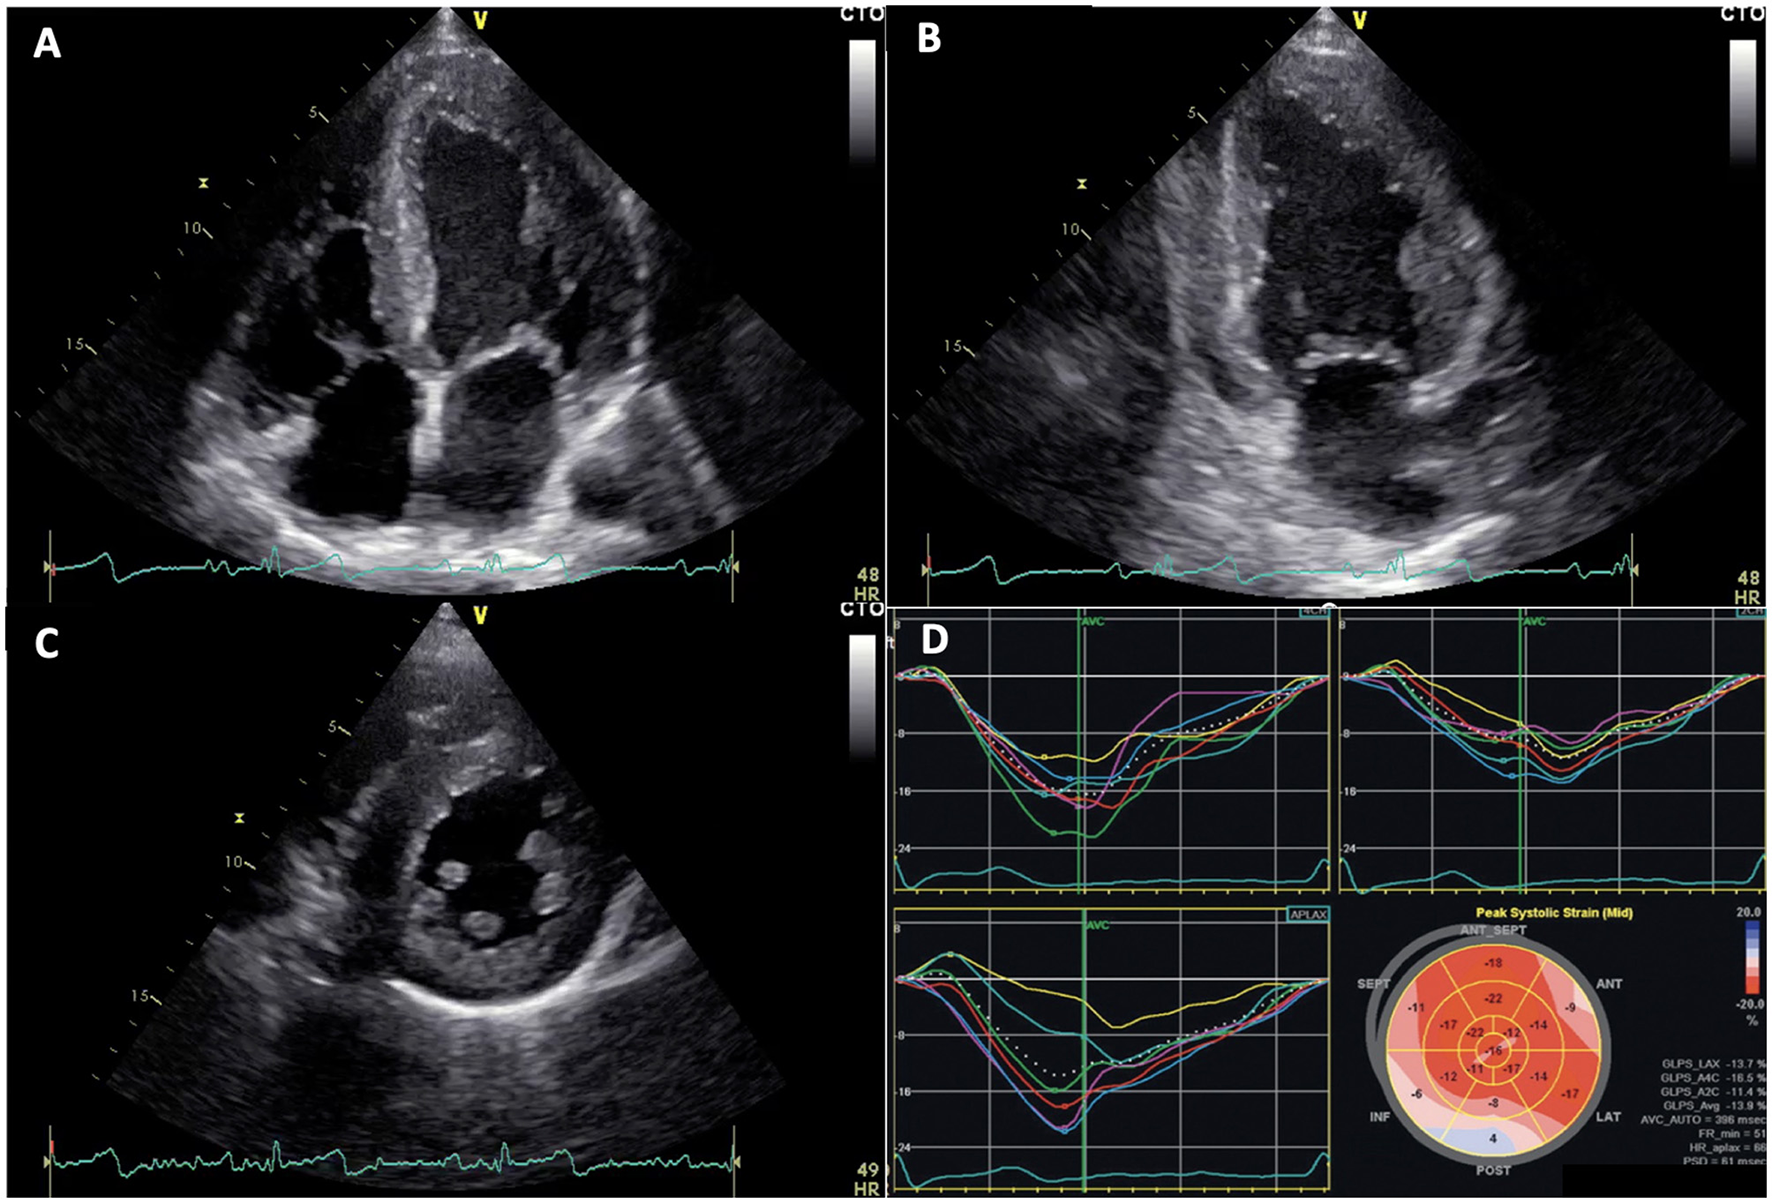

Usually, accumulation of glycosphingolipids in myocardial cells leads to ventricular remodeling and subsequent concentric hypertrophy, even if asymmetric hypertrophy has also been rarely described (9, 21). Echocardiography represents the primary diagnostic tool in detection of LVH (1) (Figure 2). However, the proportion of patients with FD who are not correctly recognized at the time of echocardiography or first medical contact is up to date still high. Despite the availability of fast and easy to perform genetic screening techniques to determine the enzymatic activity of α-Gal A or genetic mutations in the GLA gene, the real incidence of FD is probably still underestimated (6).

Figure 2

Echocardiographic images of Fabry disease (FD) patients. (A–C) apical 4 chambers, 2 chambers, and parasternal short axis views showing left ventricular concentric hypertrophy typical of FD, respectively. (D) altered global longitudinal strain in patient with FD, note inferolateral segment alterations.